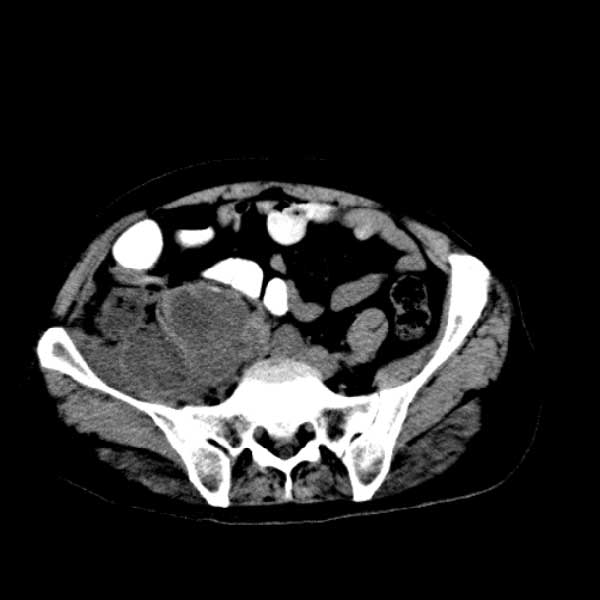

标题: CT13513:男 71 腹部疼痛20余天,近几天高热就诊,骨窗未见异 [打印本页]

考虑右侧腰大肌脓肿,向右髂窝、右腹股沟流注。

支持化脓性阑尾炎伴右髂窝脓肿、腰大肌腰方肌脓肿形成。

考虑腹腔及盆腔化脓性炎症,累及右侧髋关节及腹股沟区.

首先考虑化脓性阑尾炎伴腰大肌、腰方肌脓肿,不除外回盲部结核。

回盲部癌待排除。

患者肠镜检查考虑结肠癌,病理证实

患者肠镜检查考虑结肠癌,病理证实。肺部ct可见多发结节,考虑转移